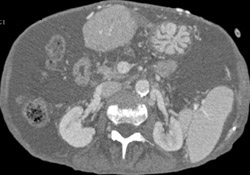

Cirrhosis With Varices as Well as Gastrostomy Tube